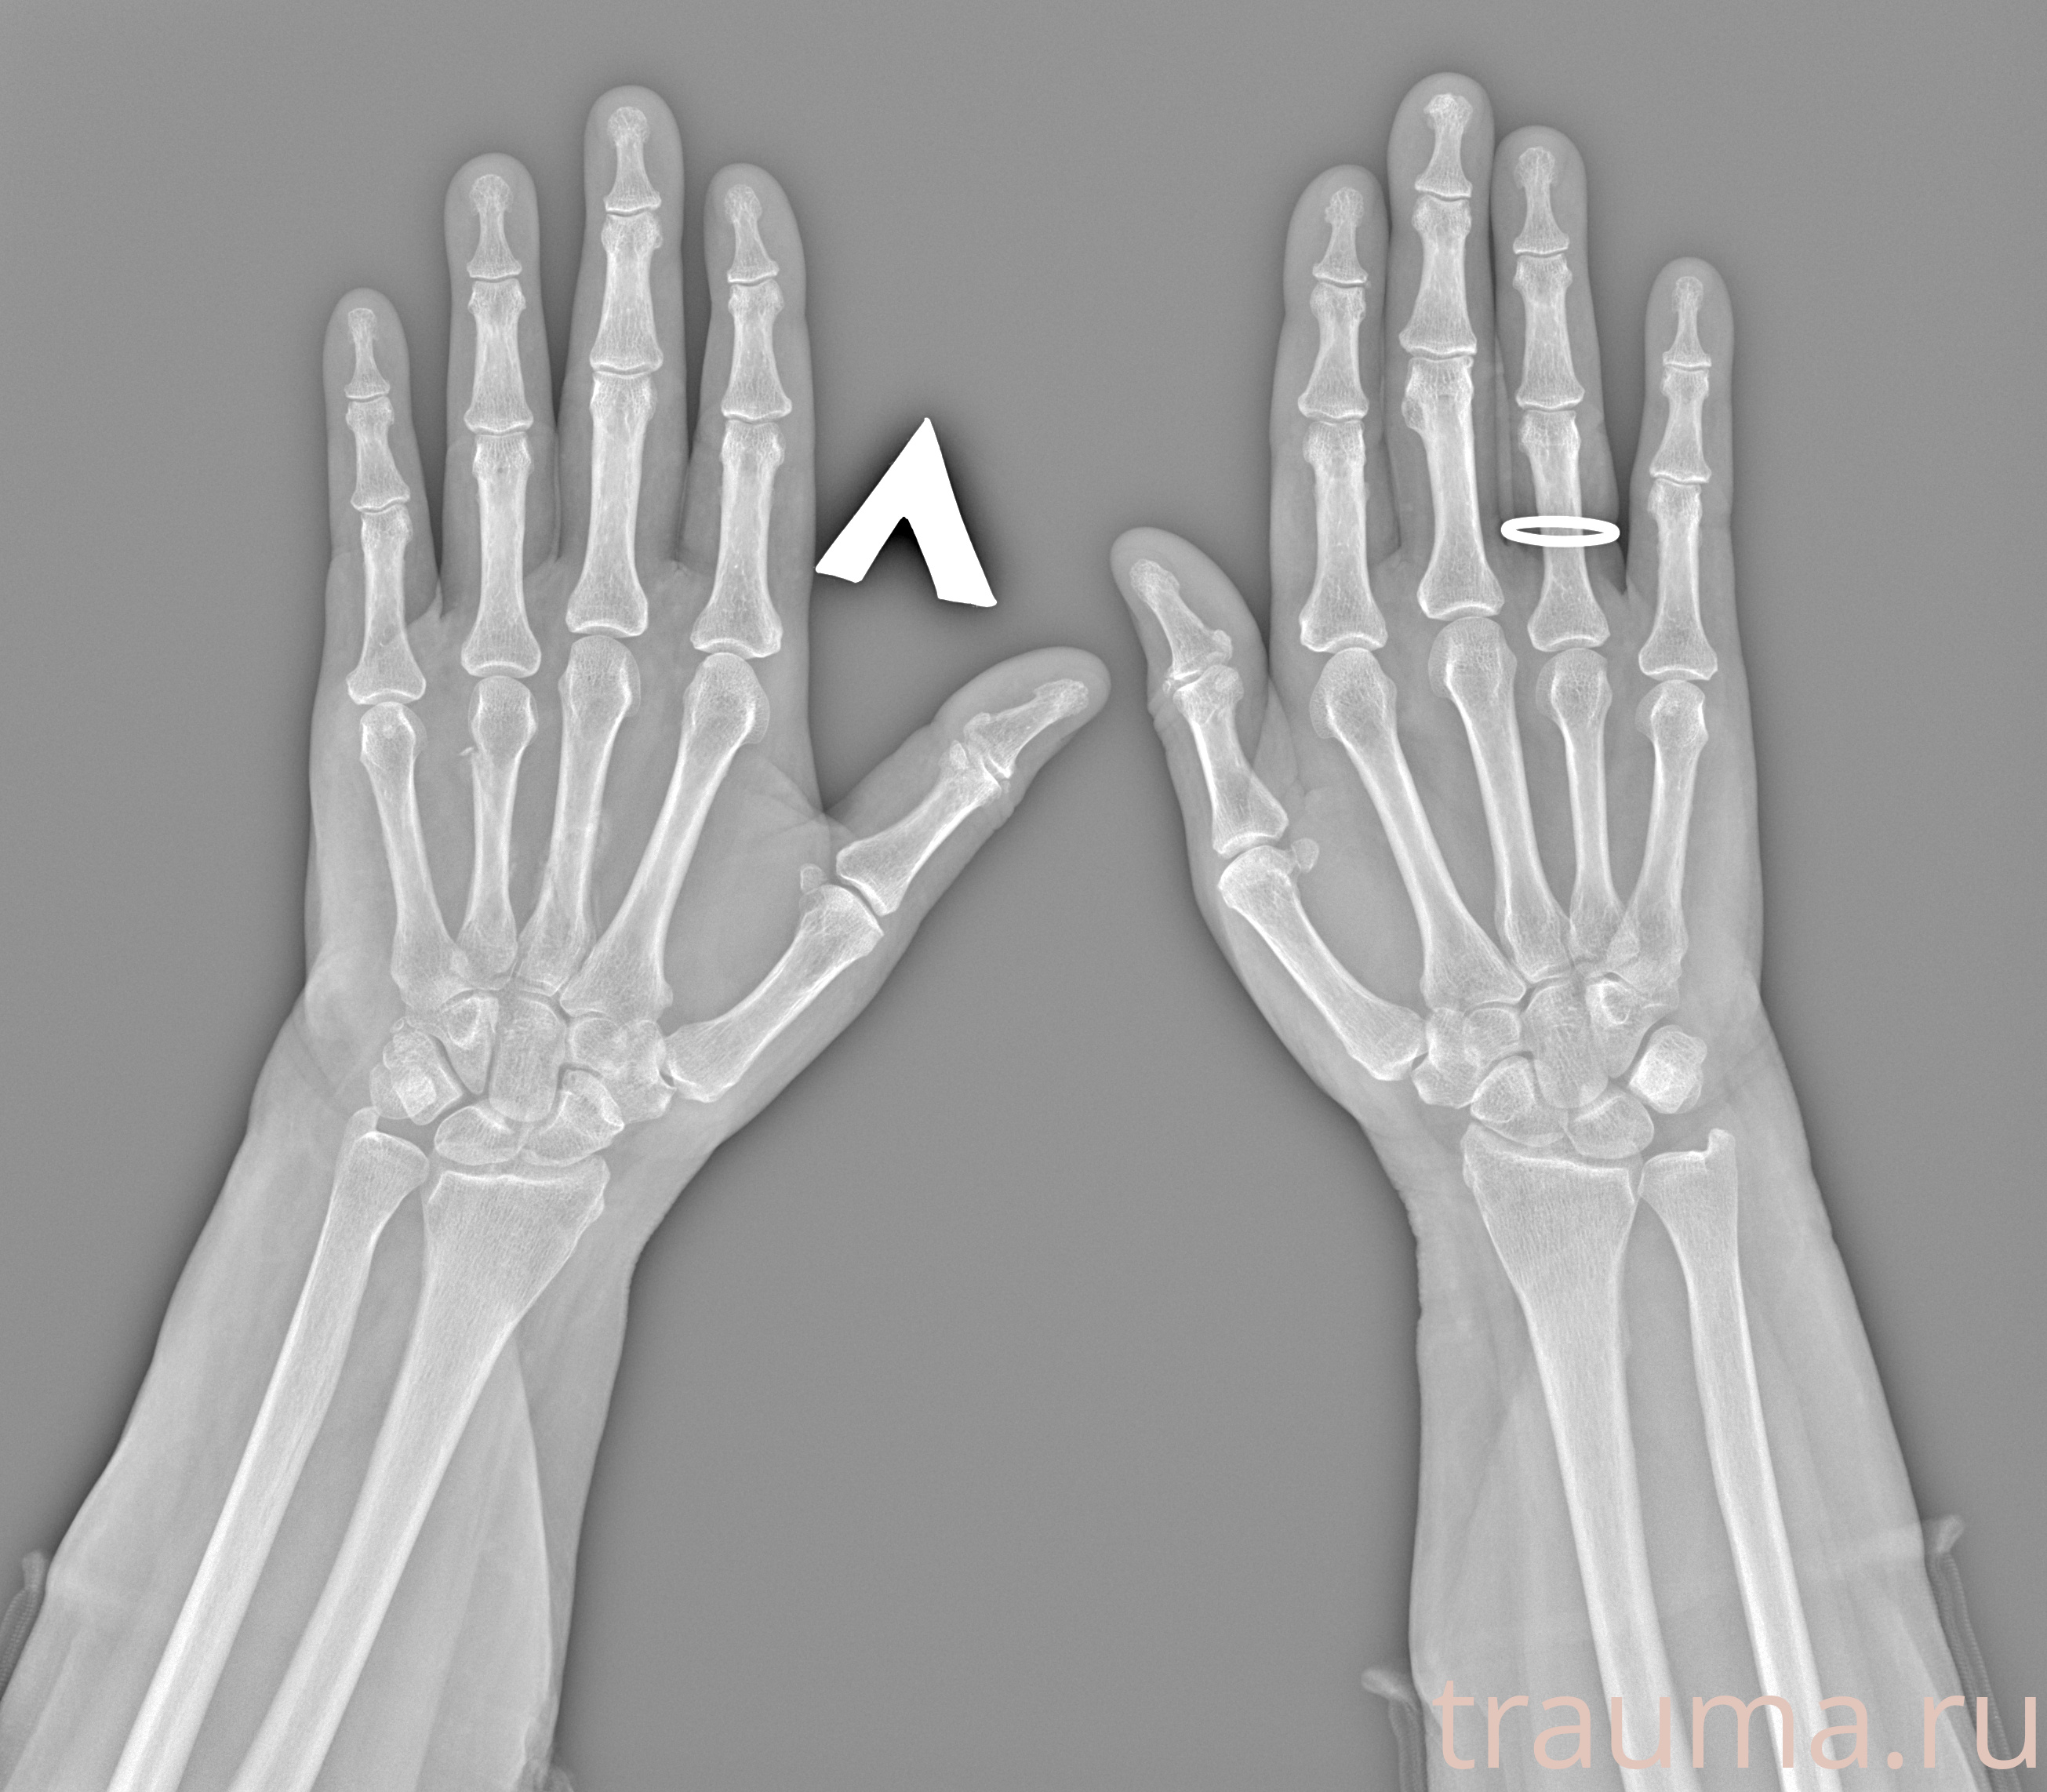

Рентгенограммы